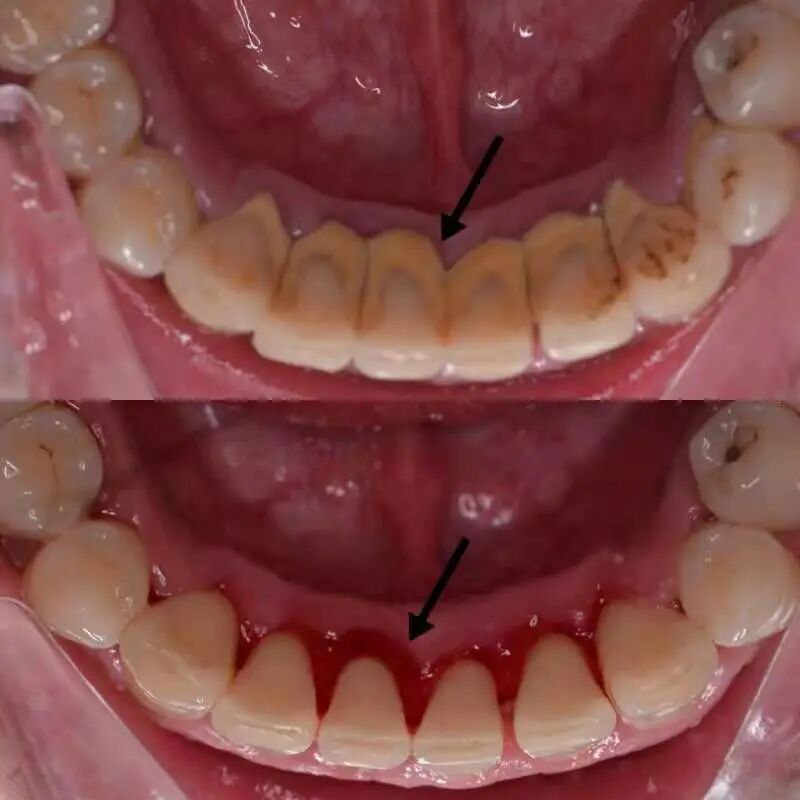

尤其是牙缝、牙齿舌面、牙周袋(见下图)

时间久了会形成牙结石

引发牙龈出血、牙龈炎、牙周炎等

(洗牙后,牙结石被清理干净。作者供图)